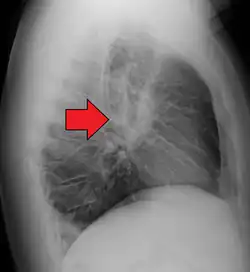

-

Hilar adenopathy especially on the person's left (AP CXR) -

Hilar adenopathy especially on the person's left (lateral CXR) -

Hilar adenopathy especially on the person's left (coronal CT) -

Hilar adenopathy especially on the person's left (transverse CT)